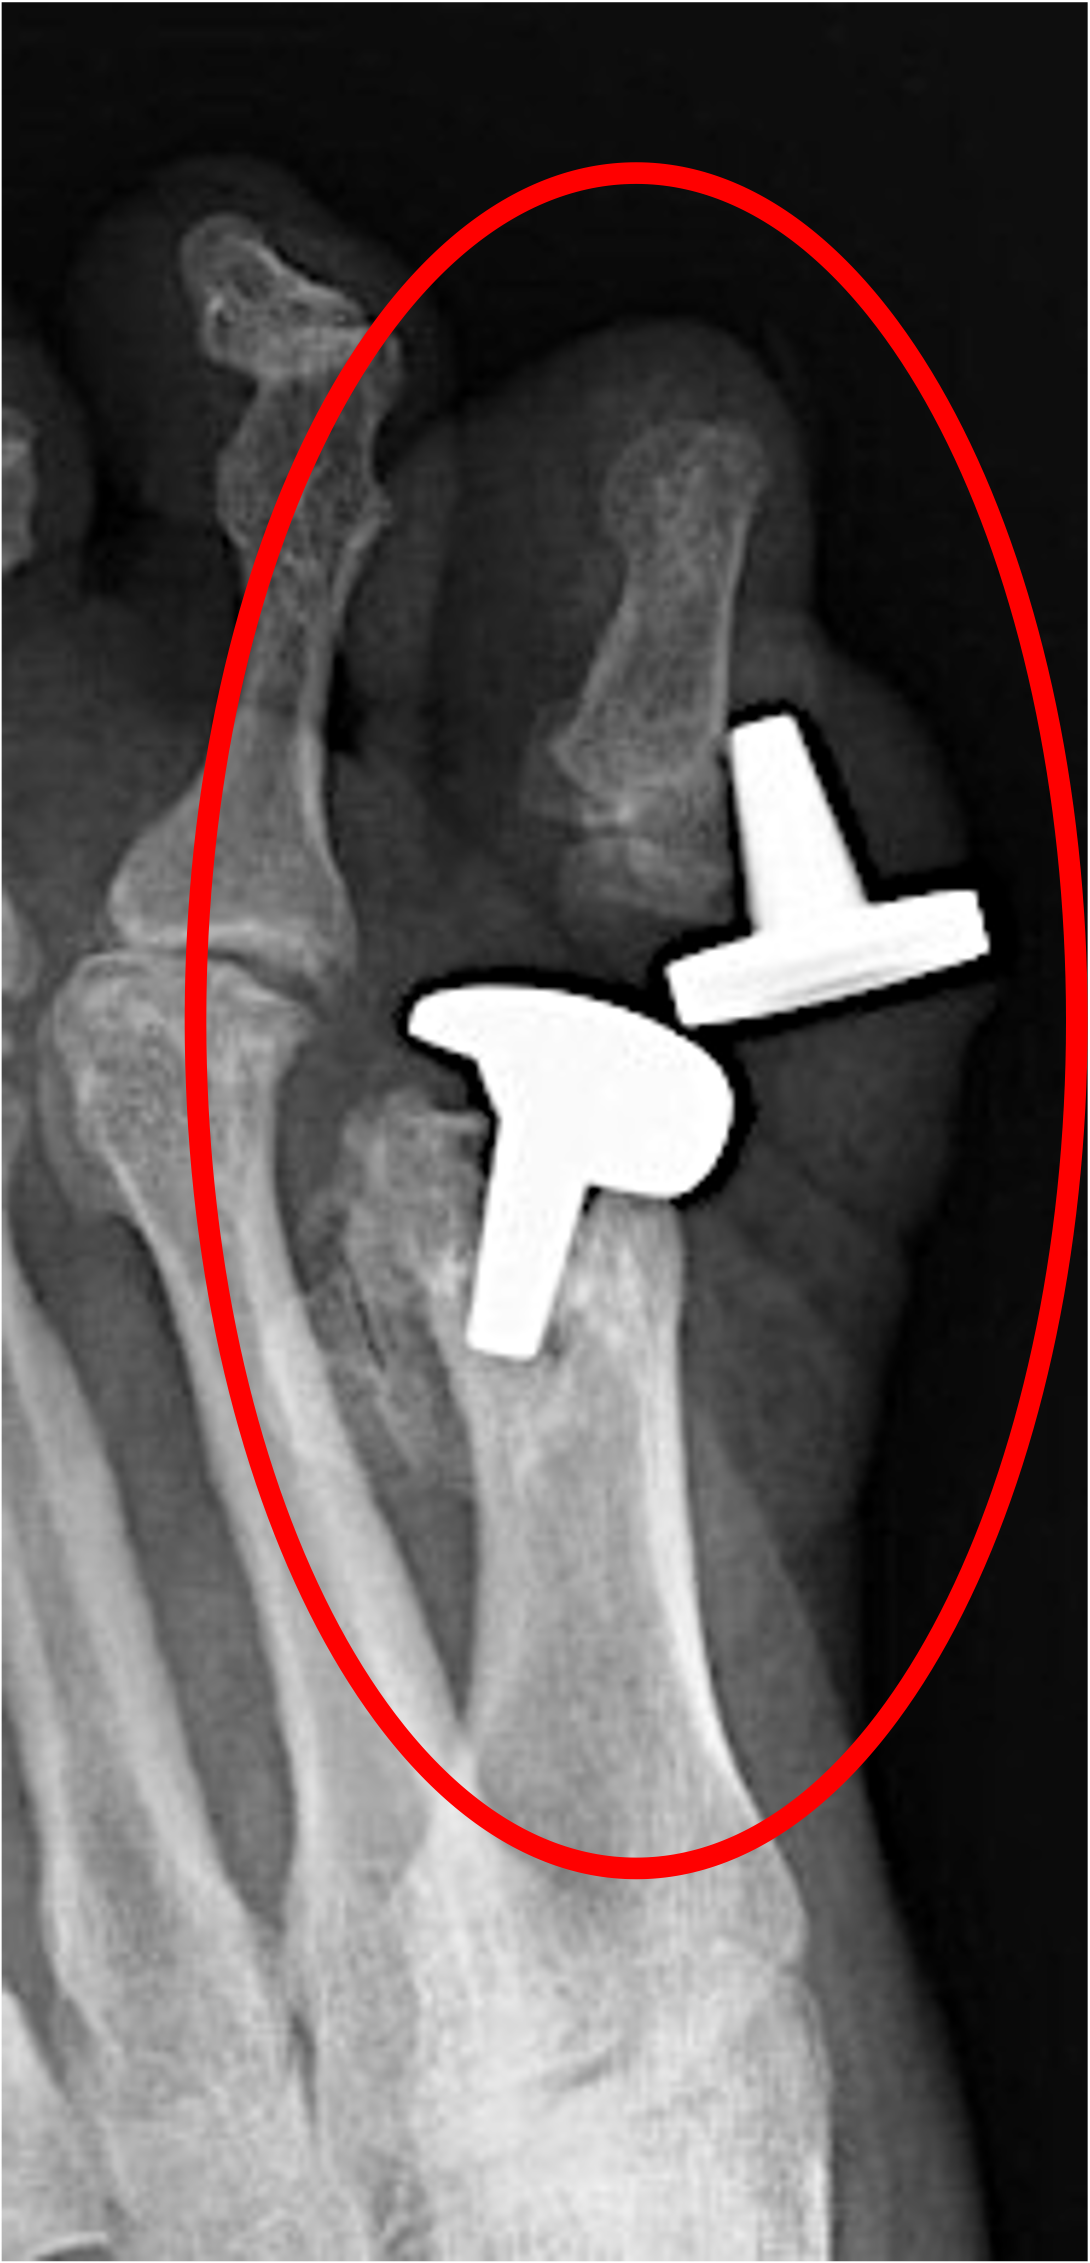

BIG TOE JOINT IMPLANT FAILURE

THERE IS A TOPIC OF REVISION SURGERY THAT COMES UP OFTEN - THE FAILED IMPLANT IN THE BIG TOE JOINT. We do see this more often than other implant failures and thankfully there are a few different procedures we can do to salvage this situation.

The big toe has two main functions - it is important for balance. Also it protects the position of the other toes. When a big toe is deformed or even missing, the other toes dont have guidance as to proper positioning and ofen develop hammertoes and then other issues develop from that.

X-ray of a big toe with two displayed damaged and ddislocated metal hardware implants, including plates and screws, identified by the red oval.